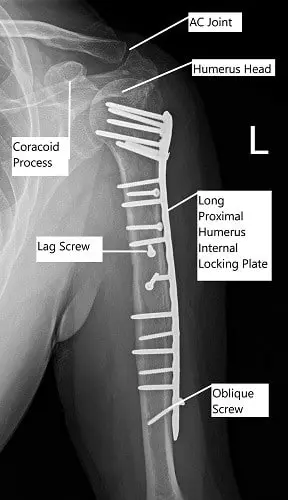

Post-operative x-ray of the left shoulder in AP view.

A lateral plate was templated. A lateral plate template was used to find that needed a 14-hole plate (2.8 mm). A 14-hole plate was opposed laterally and then, the K-wire advanced. X-ray showed good reduction and opposition. The plate was fixed distally using cortical screws.

Following that, the humeral head was fixed using multiple locking screws. Distal fixation in the mid and distal shaft was completed with a combination of locking and non-locking screws. Pictures were taken and checked and found to be satisfactory.